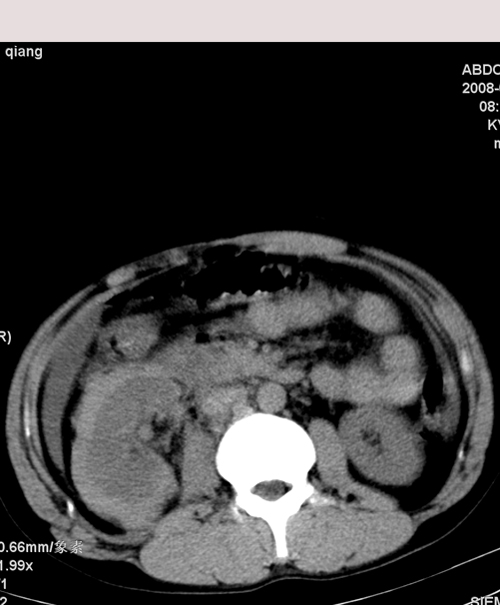

以下是引用muzi888在2008-7-15 10:45:00的发言:[br]大量腹腔积液,气腹,肾皮质弧形高密度影,诊断;1 空腔脏器穿孔 2 右肾包膜下血肿

以下是引用随光逐影在2008-7-15 11:18:00的发言:[br]考虑为:1)腹部空腔脏器穿孔。2)右肾破裂并肾包膜下血肿,肾盂积血。3)腹水(血)。